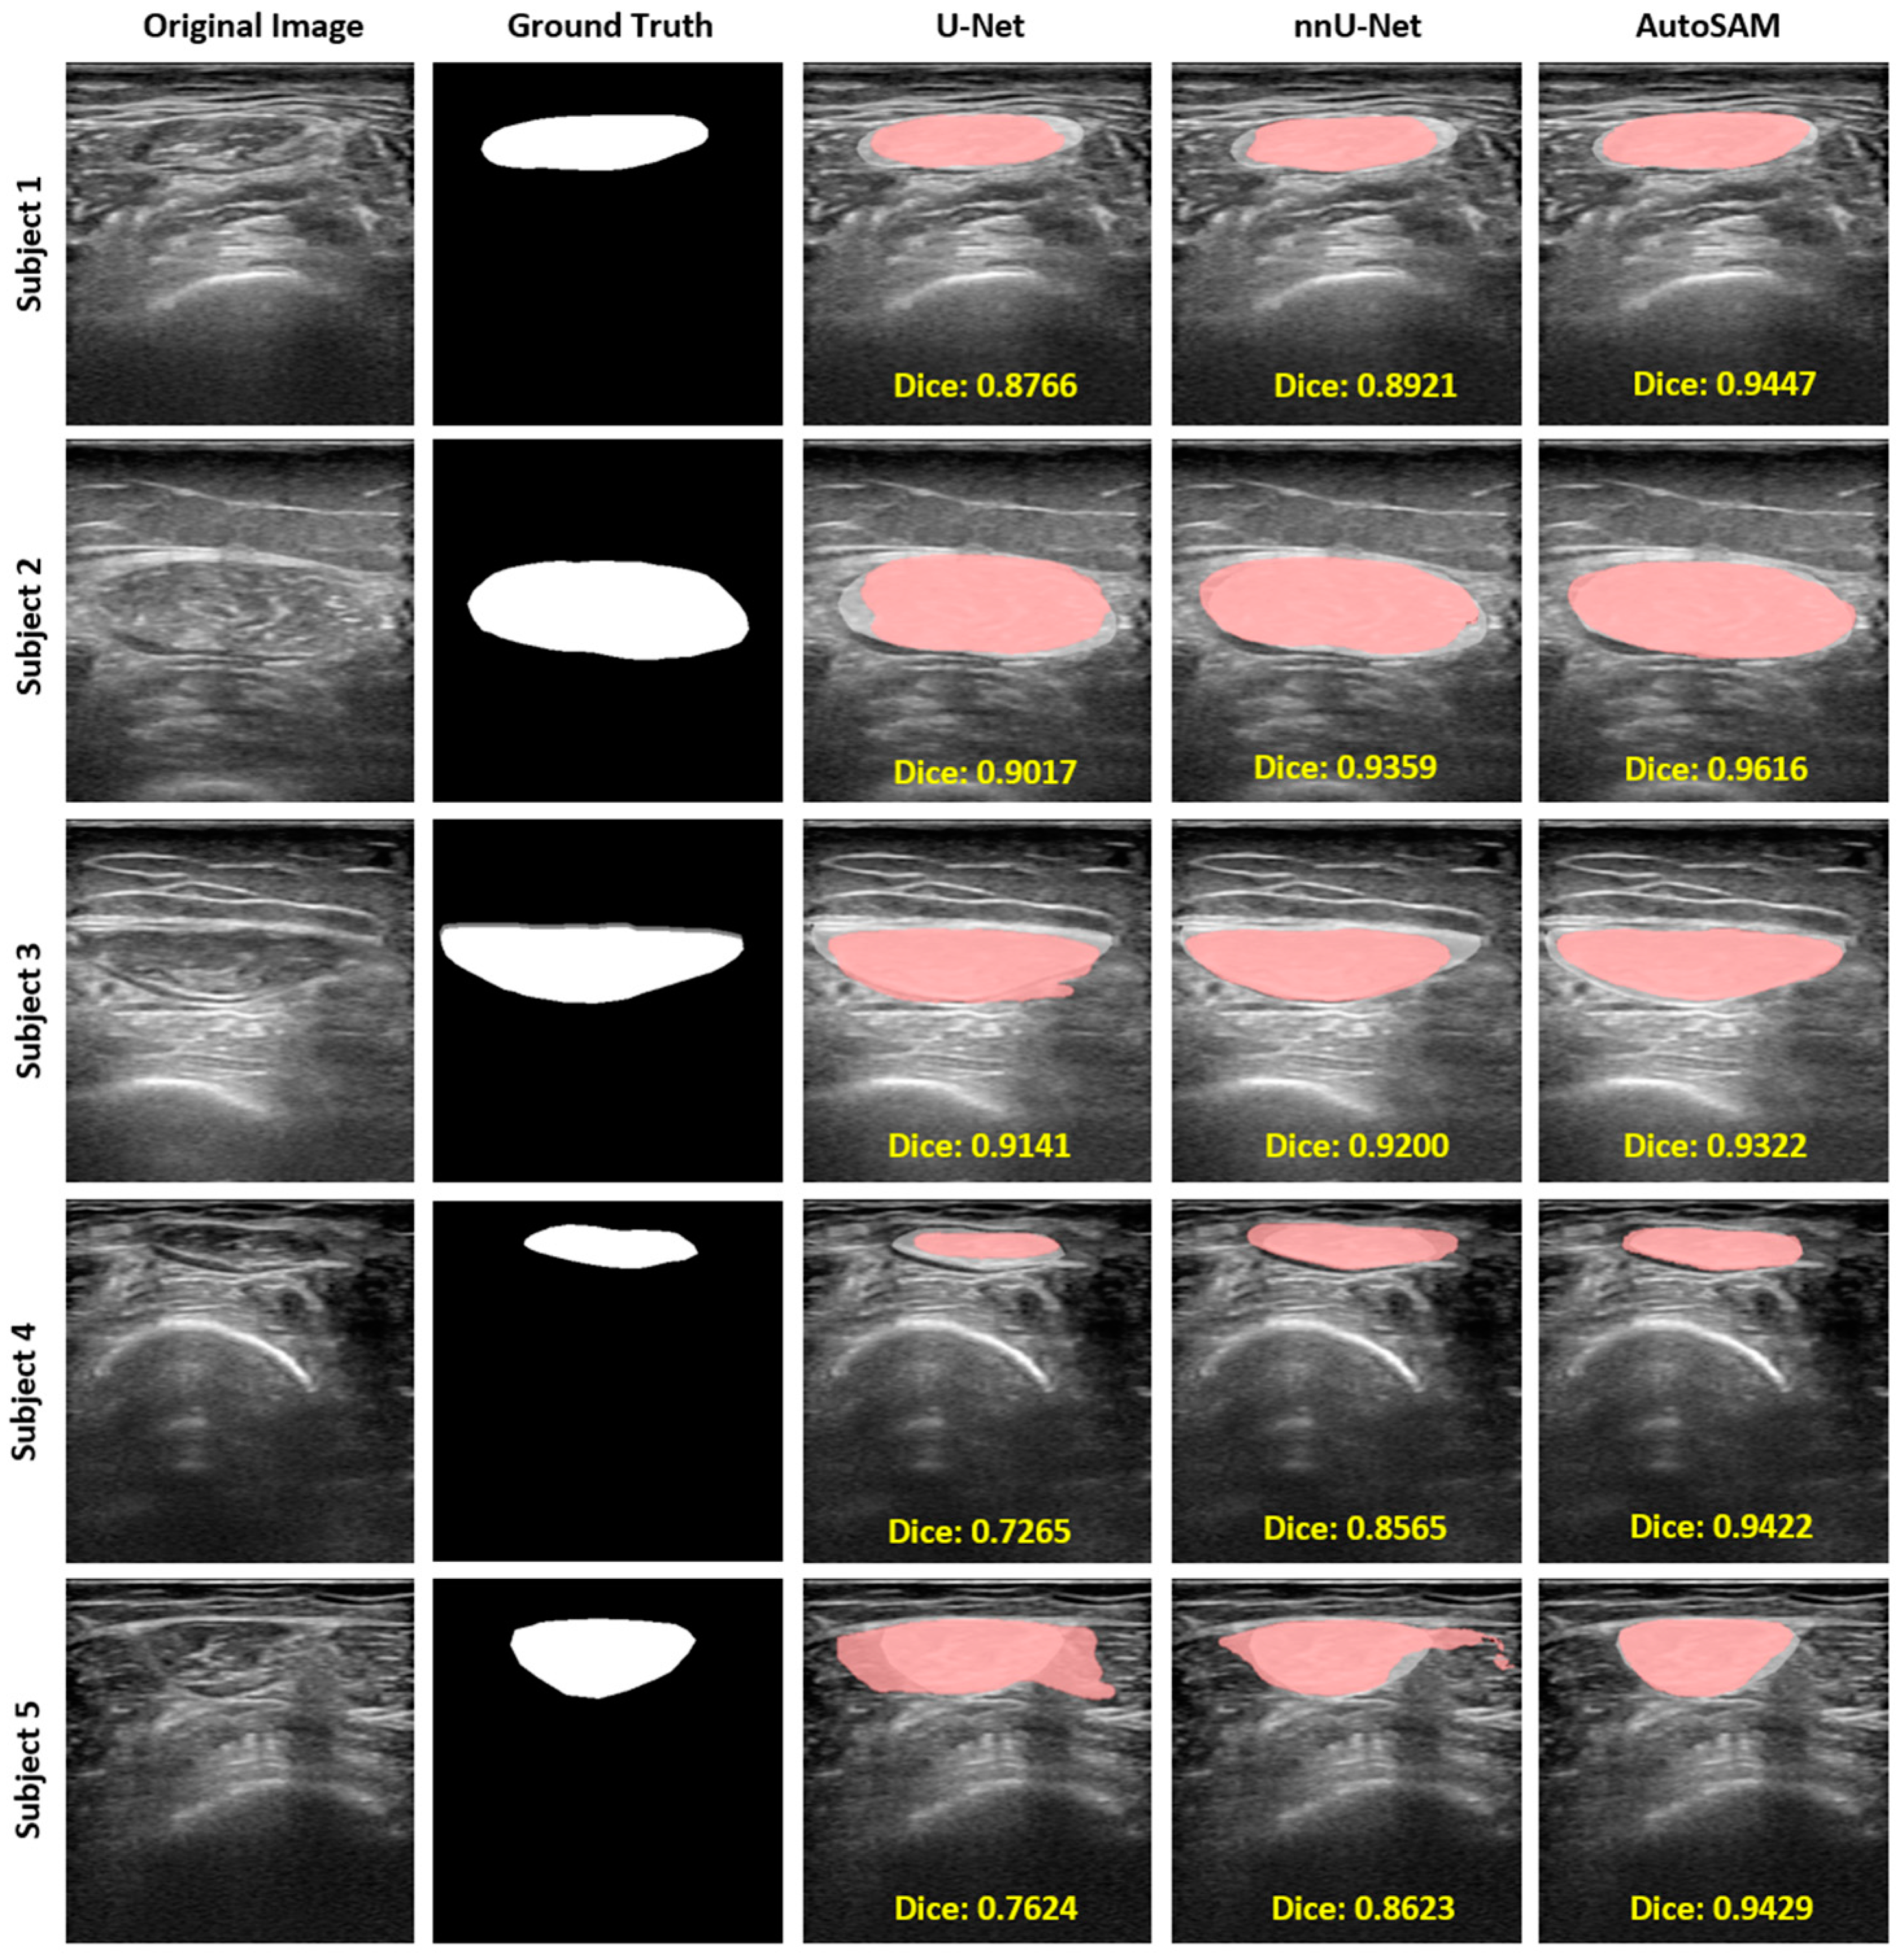

| Model | DICE | IoU | HD | Accuracy | Precision | Recall |

|---|---|---|---|---|---|---|

| U-Net | 0.8178 (SD = 0.1010) | 0.7035 (SD = 0.1371) | 4.2724 (SD = 2.6113) | 0.9637 (SD = 0.0175) | 0.9828 (SD = 0.0189)  | 0.9759 (SD = 0.0221)  |

| nnU-Net | 0.8910 (SD = 0.0610) | 0.8084 (SD = 0.0924) | 3.2074 (SD = 2.7506) | 0.9789 (SD = 0.0145) | 0.9881 (SD = 0.0143)  | 0.9884 (SD = 0.0142)  |

| Auto-SAM | 0.9205 (SD = 0.0449) | 0.8557 (SD = 0.0720) | 1.7213 (SD = 1.1670) | 0.9826 (SD = 0.0137) | 0.9897 (SD = 0.0109)  | 0.9911 (SD = 0.0141)  |